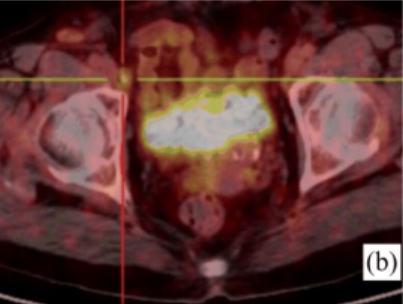

此前一位40岁的女性患者赵某某,因“发热伴皮疹1月”收入我院,患者曾于外院抗感染治疗无效,入我院后完善血常规:白细胞18.0×109/L,中性粒细胞百分比89.5%;铁蛋白4400ng/ml;血沉83mm/h;PCT0.10ng/ml;CRP82mg/L;抗核抗体谱、类风湿因子、抗“O”、肿瘤标志物、结核抗体、T-SPOT、血培养、腹部彩超等均未见异常,胸部CT提示肺部纤维灶,进一步完善骨髓穿刺、骨髓活检亦无明显异常,为明确患者发热伴皮疹原因,进一步行PET/CT检查,结果提示双侧腋窝、右侧髂外血管旁及双侧腹股沟区多发肿大淋巴结,局部淋巴结病灶FDG代谢轻度增高,考虑非特异性炎性改变。综合结合患者相关表现、检查以及排除其他病因,相关学科讨论后,初步考虑为成人still病,予以糖皮质激素治疗后皮疹消退、体温降至正常,病情平稳后带药出院。

图为患者赵女士的PET/CT融合成像显示腋窝、腹股沟淋巴结FDG摄取增高